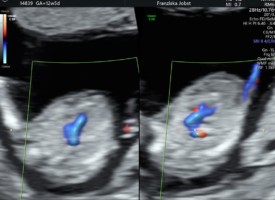

Dopplersonographie der mütterlichen und kindlichen Gefäße:

Die Dopplersonographie ist ein Ultraschallverfahren zur Untersuchungen von mütterlichen und kindlichen Blutflüssen. Eingesetzt wird diese weiterführende Untersuchung bei Verdacht auf eine Funktionsstörung des Mutterkuchens,verzögertem Wachstum des Kindes oder Bluthochdruck in der Schwangerschaft. Die Untersuchung gibt genaue Informationen über akute oder chronische Mangelzustände der Plazenta sowie Wachstumsstörungen des Kindes. Am Aussagekräftigsten ist die Durchführung zwischen der 24- 36 SSW zur fetalen Überwachung.